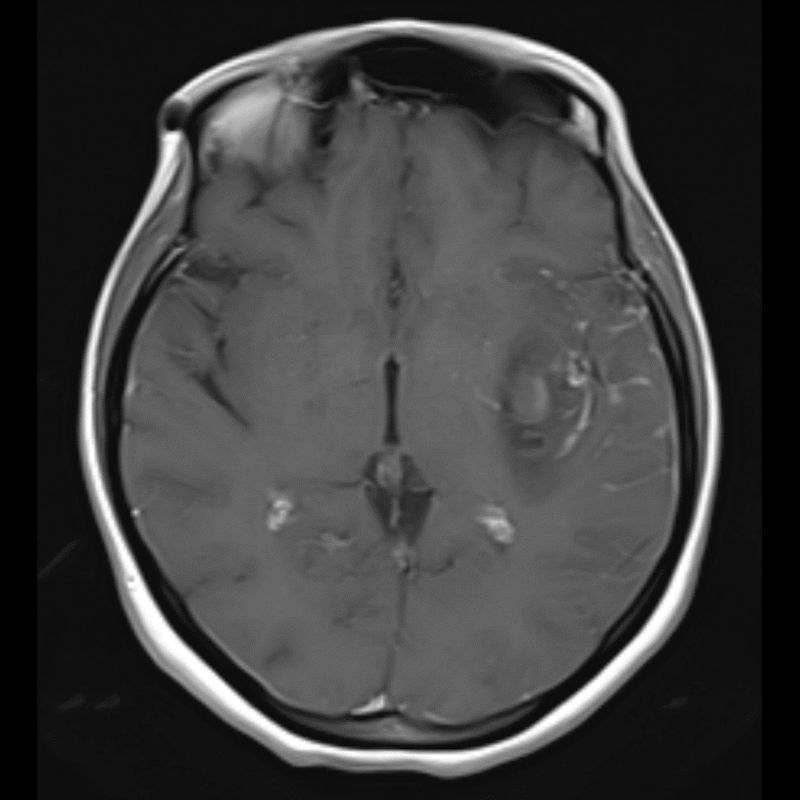

40 yaş, K

Ateş, bir haftadır artan baş ağrısı, yeni gelişen bilinç bulanıklığı

Sol MCA Segmet M2-3’te Sakküler Mikotik Anevrizma Rüptürü

Enfekte intrakraniyal anevrizma rüptürü